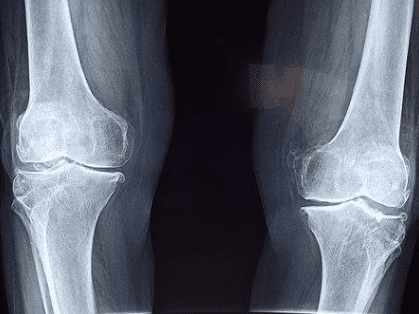

- 단순방사선이나 관절경 검사 등에서 관절연골 소실이 확인되어 치료가 힘든 퇴행성 관절염

- 만 60세 ~ 만 64세 이하 : Kellgren Lawrence grade 5 (퇴행성 관절염 5단계)

- 만 65세 이상 : Kellgren Lawrence grade 3단계 이상 - 타 수술(인대재건술 등)의 실패로 다발성 인대손상으로 인한 슬관절의 심한 불안정성